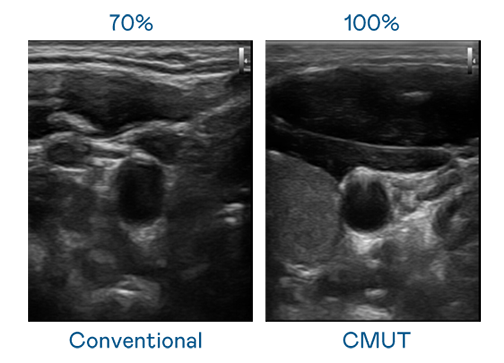

CMUT ¼¼ÊõÊÇÒ»ÖÖÓõçÈÝʽ΢»úµçÔª¼þÀ´²úÉú³¬Òô²¨Ñ¶ºÅµÄ¼¼Êõ¡£Ó봫ͳ PZT ѹµçʽ¼¼ÊõÏà±È£¬CMUT Ƶ¿íÔö¼Ó 30%£¬¸ü¿íƵµÄ³¬Òô²¨Ñ¶ºÅÈÃÓ°Ïñ½âÎö¶È´ó·ùÌáÉý£¬ÊÇʵÏÖ¸ßÓ°ÏñÆ·ÖÊÒ½ÁƳ¬Òô²¨É¨Ãè¡¢´Ù½ø¾«×¼Ò½ÁÆ·¢Õ¹µÄ¹Ø¼ü¼¼Êõ¡£

´óƵ¿í´øÀ´³¬ÇåÎúÓ°Ïñ

³¬Òô²¨Ó°ÏñµÄ½âÎö¶È¸ßµÍ£¬Ê×ÏÈÈ¡¾öÓÚ̽ͷÄÜ·¢³öµÄѶºÅƵ¿í¡£ÓÀÓ¯»á CMUT ¿ÉÌṩ¸ßÇåÎúµÄ³¬Òô²¨Ñ¶ºÅ£¬Ìṩ¸ßƵ¿í¡¢¸ßÁéÃô¶È¡¢Ó°ÏñÎÆÀíϸ½Ú¸ü¸ßµÄ³¬Òô²¨Ó°Ïñ£¬ÐÖúÒ½»¤ÈËÔ±Ëõ¶ÌÓ°ÏñÅжÁʱ¼ä¼°ÀûÓþ«×¼µÄÒ½ÁÆÓ°Ïñ½øÐÐÕï¶Ï¡£